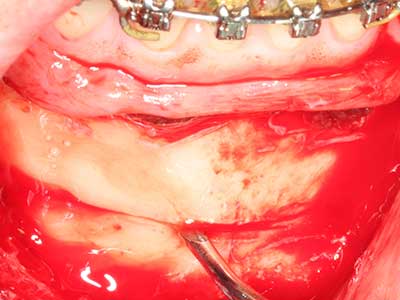

La piezochirurgia presenta altri vantaggi per quanto riguarda la raccolta di blocchi ossei. Oltre all'elevata precisione dell'osteotomia appena descritta, l'utilizzo di puntine per sega molto sottili permette di minimizzare in maniera significativa la perdita di materiale. È molto probabile che si verifichi una maggiore perdita di materiale durante la raccolta utilizzando puntine di strumenti più spessi, in particolare delle frese Lindemann (Lakshmiganthan, Gokulanathan et al. 2012). La separazione basale, necessaria in particolare per i trapianti di blocchi nella zona retromolare, viene semplificata grazie a seghe specificatamente progettate di forma rettangolare; di conseguenza la piezochirurgia è considerata una procedura precisa, semplice e sicura per la raccolta di blocchi di osso nella zona retromolare (Happe 2007) (figg. 1-12).

Indicazione: incisione ossea

Il tessuto osseo non è semplicemente una struttura minerale, ma contiene anche una percentuale significativa di fibre di collagene. Ciò significa che non possiede solo una buona forza di compressione, ma anche un certo livello di flessibilità che è possibile sfruttare durante l'esecuzione degli accrescimenti di osso. Nella procedura di espansione classica con incisione ossea, la cresta alveolare atrofizzata viene incisa longitudinalmente ed espansa con cautela dopo aver raggiunto una profondità di osteotomia adeguata (figg. 13-16), idealmente senza una sostanziale rimozione del periostio (Brugnami, Caiazzo et al. 2014, Stricker, Fleiner et al. 2014). I sistemi a piastra e vite con distanza di espansione incrementale si sono dimostrati efficaci nella separazione delle due lamelle ossee restando al di sotto della soglia di frattura. In generale, sono richieste larghezze dell'osso residuo di almeno 3-4 mm (Chiapasco, Zaniboni et al. 2006) per garantire un'adeguata flessibilità e una copertura sufficiente dell'osso per gli impianti futuri. Se necessario, un'osteotomia di rilascio verticale su uno o più lati può migliorare la flessibilità. Una combinazione con ulteriori tecniche di accrescimento, in particolare dal lato buccale, è stata descritta come un'alternativa alla tecnica classica.

La procedura di incisione è particolarmente atraumatica e non comporta una perdita significativa di dimensione durante l'utilizzo delle seghe piezoelettriche, così come non si notano differenze rilevanti tra impianti in mandibole incise e impianti in una cresta alveolare senza deficit osseo (Chiapasco, Zaniboni et al. 2006, Danza, Guidi et al. 2009). Una sufficiente irrigazione continua è essenziale, tuttavia, in particolare con incisione profonda e localmente ristretta, per prevenire la sollecitazione termica nelle regioni apicali dell'osteotomia.